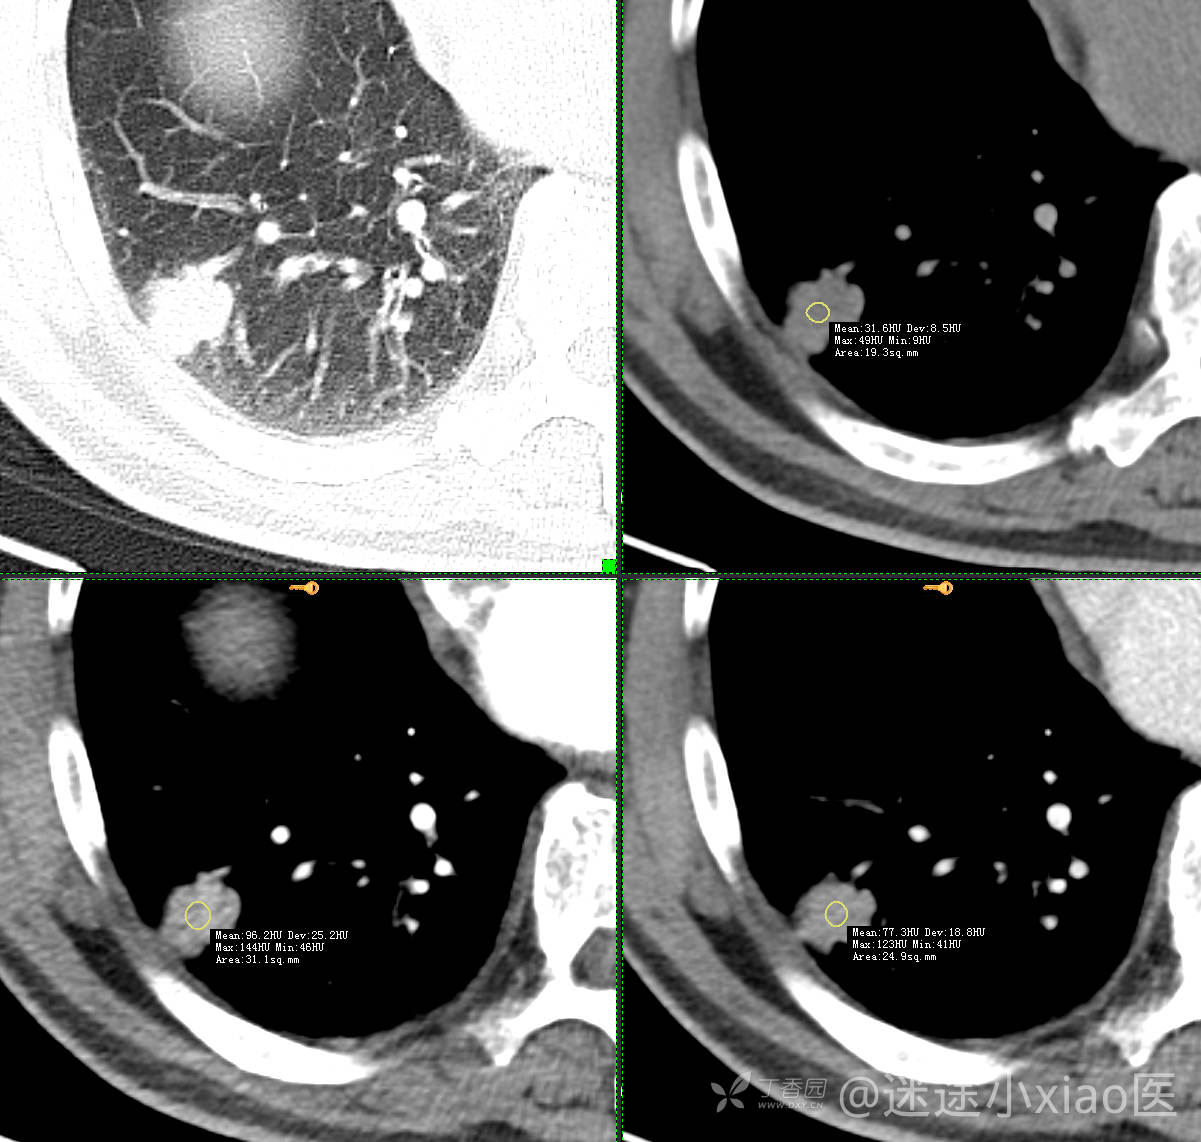

胸组50:老年男性,发现肺占位一天,(结果公布)

主诉: 发现右肺占位1天

现病史: 患者诉1日前在当地医院检查时胸部CT示;肺结节(具体不详),当时无胸闷气急。 无咳嗽咳痰,无胸痛,无恶心呕吐等。今为求进一步治疗,门诊拟“肺结节”收治入院。病来,患者神志清,精神可,胃纳睡眠可,二便无殊,体重无明显增减。